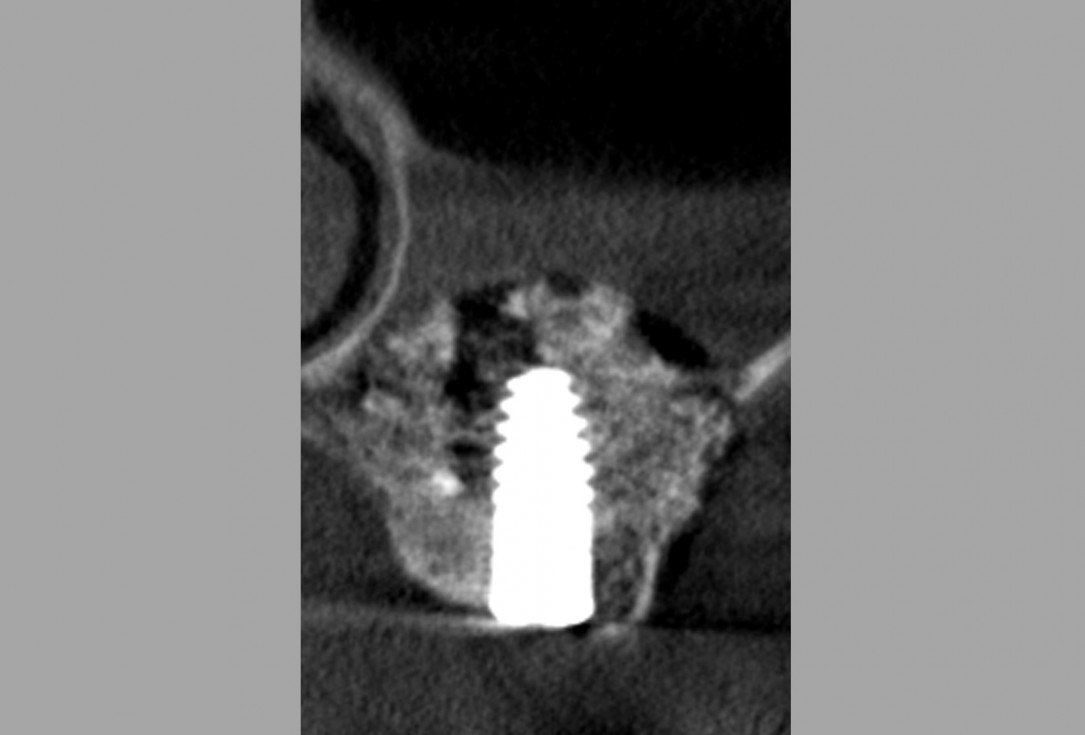

15/16 - Alveolar ridge and sinus floor CT scan immediately after the surgery

Lateral sinus lift one-stage with cerabone® & collprotect® membrane - Dr. V. Kalenchuk